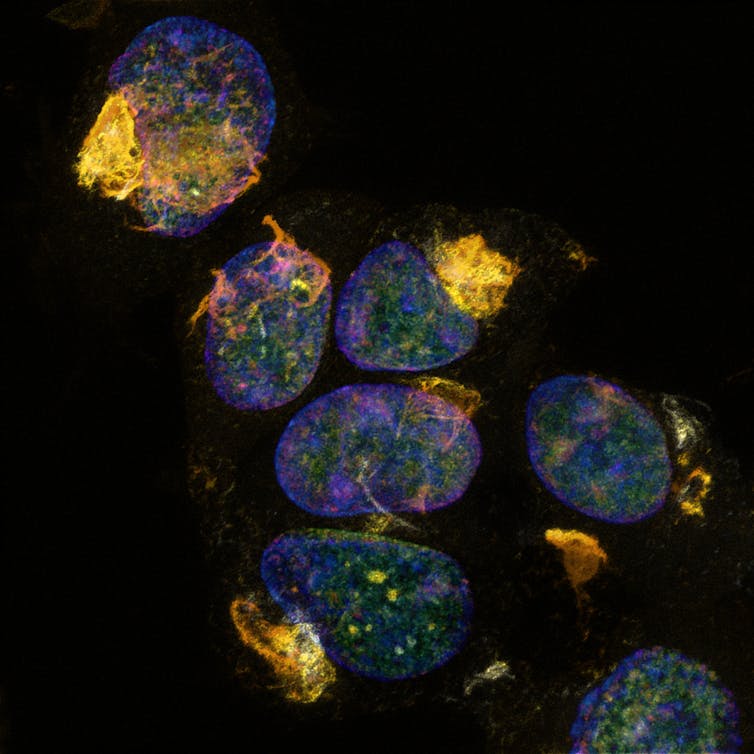

In Alzheimer’s disease, tau protein (gold) becomes toxic as it builds up. It’s hard to believe these mesmerising, gem-like clusters can be so destructive.